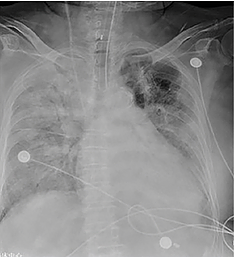

CASO 2

Paciente de 79 años, género femenino, presentó dolor torácico, tos y fiebre de tres días de evolución. Dos miembros de su familia habían sido diagnosticados de COVID-19 recientemente. La paciente desarrolló el Síndrome de Dificuldad Respiratoria Aguda en los días siguientes y falleció once días después de su ingreso.